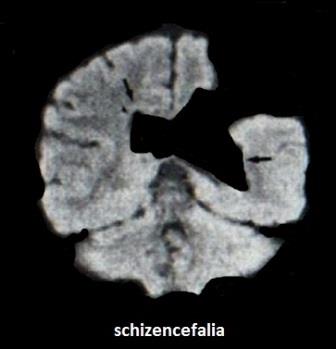

La schizencefalia è conseguenza della precoce interruzione dello sviluppo degli emisferi cerebrali con formazione di una fessura (schisi) che mette in comunicazione i ventricoli cerebrali laterali con gli spazi liquorali periferici.Tali comunicazioni possono essere a "labbra aperte" o a "labbra chiuse", unilaterali o bilaterali. La definizione a labbra aperte o chiuse si riferisce all'apposizione o meno della corteccia cerebrale adiacente alla fessura.

Tale caratteristica delinea due forme di Schizencefalia:

Schizencefalia tipo I caratterizzata da comunicazioni strette e labbra fuse in alcuni settori;

Schizencefalia tipo II caratterizzata da comunicazioni più ampie, labbra aperte e formazione di una cavità riempita da abbondante liquido cerebrospinale.

Il secondo tipo è l'unico riportato in letteratura in diagnosi prenatale ed è caratterizzato da una schisi che si estende dalla superficie corticale ai ventricoli laterali dilatati. La sede più comune è la scissura silviana. E' frequente (50-75% dei casi) l'associazione con la Displasia setto-ottica. Inoltre vi è correlazione tra topografia lobare delle fessure e presenza o meno del setto pellucido: tutti i casi con setto pellucido assente presentano fessure nel lobo frontale, mentre tutti i casi con setto pellucido presente hanno fessure a livello dei lobi parietale, temporale e occipitale.

La diagnosi prenatale, possibile formularla tardivamente nel III trimestre, difficile, potrebbe essere facilitata con l'ausilio della tecnica 3D/4D che permette di ottenere contemporaneamente immagini nelle varie proiezioni spaziali, in modo particolare la sezione coronale.